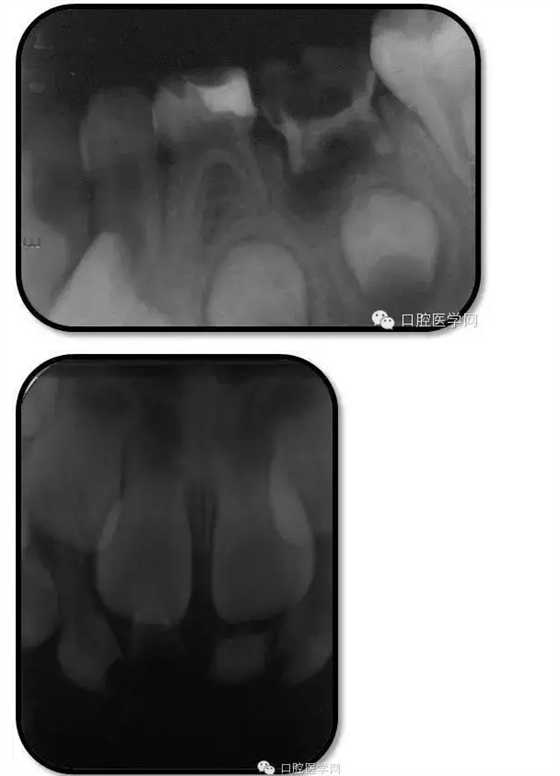

臨床檢查: 75OL齲洞, 舌側(cè)牙體完全劈裂斷端齊齦,探及大量軟化腐質(zhì)。頰側(cè)牙齦紅腫見瘺管,擠壓大量溢膿。叩(±),不松動。X線:75根管空虛,牙根吸收約1/2,根尖周及根分歧大面積透射影,35發(fā)育4期,骨硬板尚連續(xù);51殘根,唇側(cè)牙齦瘺管,叩(±),不松動。X線:51牙根吸收約1/2,根尖周低密度影。

85O、84DO充填體邊緣不密合,叩(±),不松動。84頰側(cè)牙齦略紅腫。X線:84遠(yuǎn)中根及髓室底完全吸收,根分歧透射影,近中根內(nèi)側(cè)見外吸收,44上方骨硬板連續(xù)。85近中根完全吸收,髓室底吸收,根分岐透射影,遠(yuǎn)中根管內(nèi)見根充影像。45發(fā)育4期,骨硬板連續(xù)。

1、根分歧處病變姑息保留牙的治療及轉(zhuǎn)歸。 75牙體缺損過大,根分岐大面積透射影并累及根尖周。故拔除后間隙保持。84、85初診時已做過根管治療,有繼發(fā)齲,牙根吸收較多,可見大面積的根分歧病變,但根尖無病變,考慮44、45表面骨硬板連續(xù),故只對患牙進行了繼發(fā)齲充填治療,姑息保留。3個月復(fù)查時,85O、84DO充填完好,邊緣密合,叩(-),不松,齦無紅腫。7個月復(fù)查時85O、84DO充填完好,邊緣密合,叩(-),不松,齦無紅腫。X線:84、85根分歧透射影,44、45骨硬板連續(xù)。 回顧整個治療過程,應(yīng)定期復(fù)查84、85姑息保留牙,且間隔時間不宜過長。觀察根分歧病變的恢復(fù)情況,一旦發(fā)現(xiàn)恒牙胚受累及,則需采取積極措施。

2、75OL、85O、84DO發(fā)生根尖及根分歧病變原因 追溯75OL、85O、84DO就診之前病史,84是因慢性根尖周炎1年前行根管治療,治療當(dāng)時根充滿。75、85因慢性牙髓炎1年前行根管治療,治療當(dāng)時根充滿。這幾個牙當(dāng)時牙體缺損均較大,未行預(yù)成冠修復(fù),隨后充填體脫落,發(fā)生繼發(fā)齲,患兒1年一直未定期復(fù)診,導(dǎo)致口腔內(nèi)感染通過冠方造成根分歧和根尖的炎癥。所以總結(jié)以上,對于大面積齲壞牙根管治療后應(yīng)定期復(fù)查,并行預(yù)成冠修復(fù)。